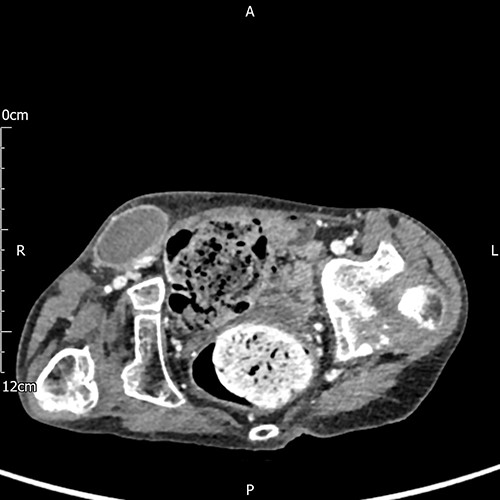

A 17-year-old boy with a history of cerebral palsy, learning disabilities and asthma who is wheelchair-bound (WHO Performance Status 4) presented with a 24-hour history of general malaise and pain in the right groin. On examination, a swollen and painful, right inguinal mass was detected, and the scrotum was found to be empty and hypoplastic on both sides. The family was reportedly unaware of the possibility of undescended or vanished testicles. The patient was urgently evaluated for a complicated right inguinal hernia and computed tomography (CT) scan of the abdomen (Fig. 1) demonstrated a mass in the right groin that lacked classical radiological features of a hernia.

A subcutaneous encapsulated soft tissue mass was described in the right groin raising the suspicion of neoplasia, nodal enlargement or hematoma (axial view).